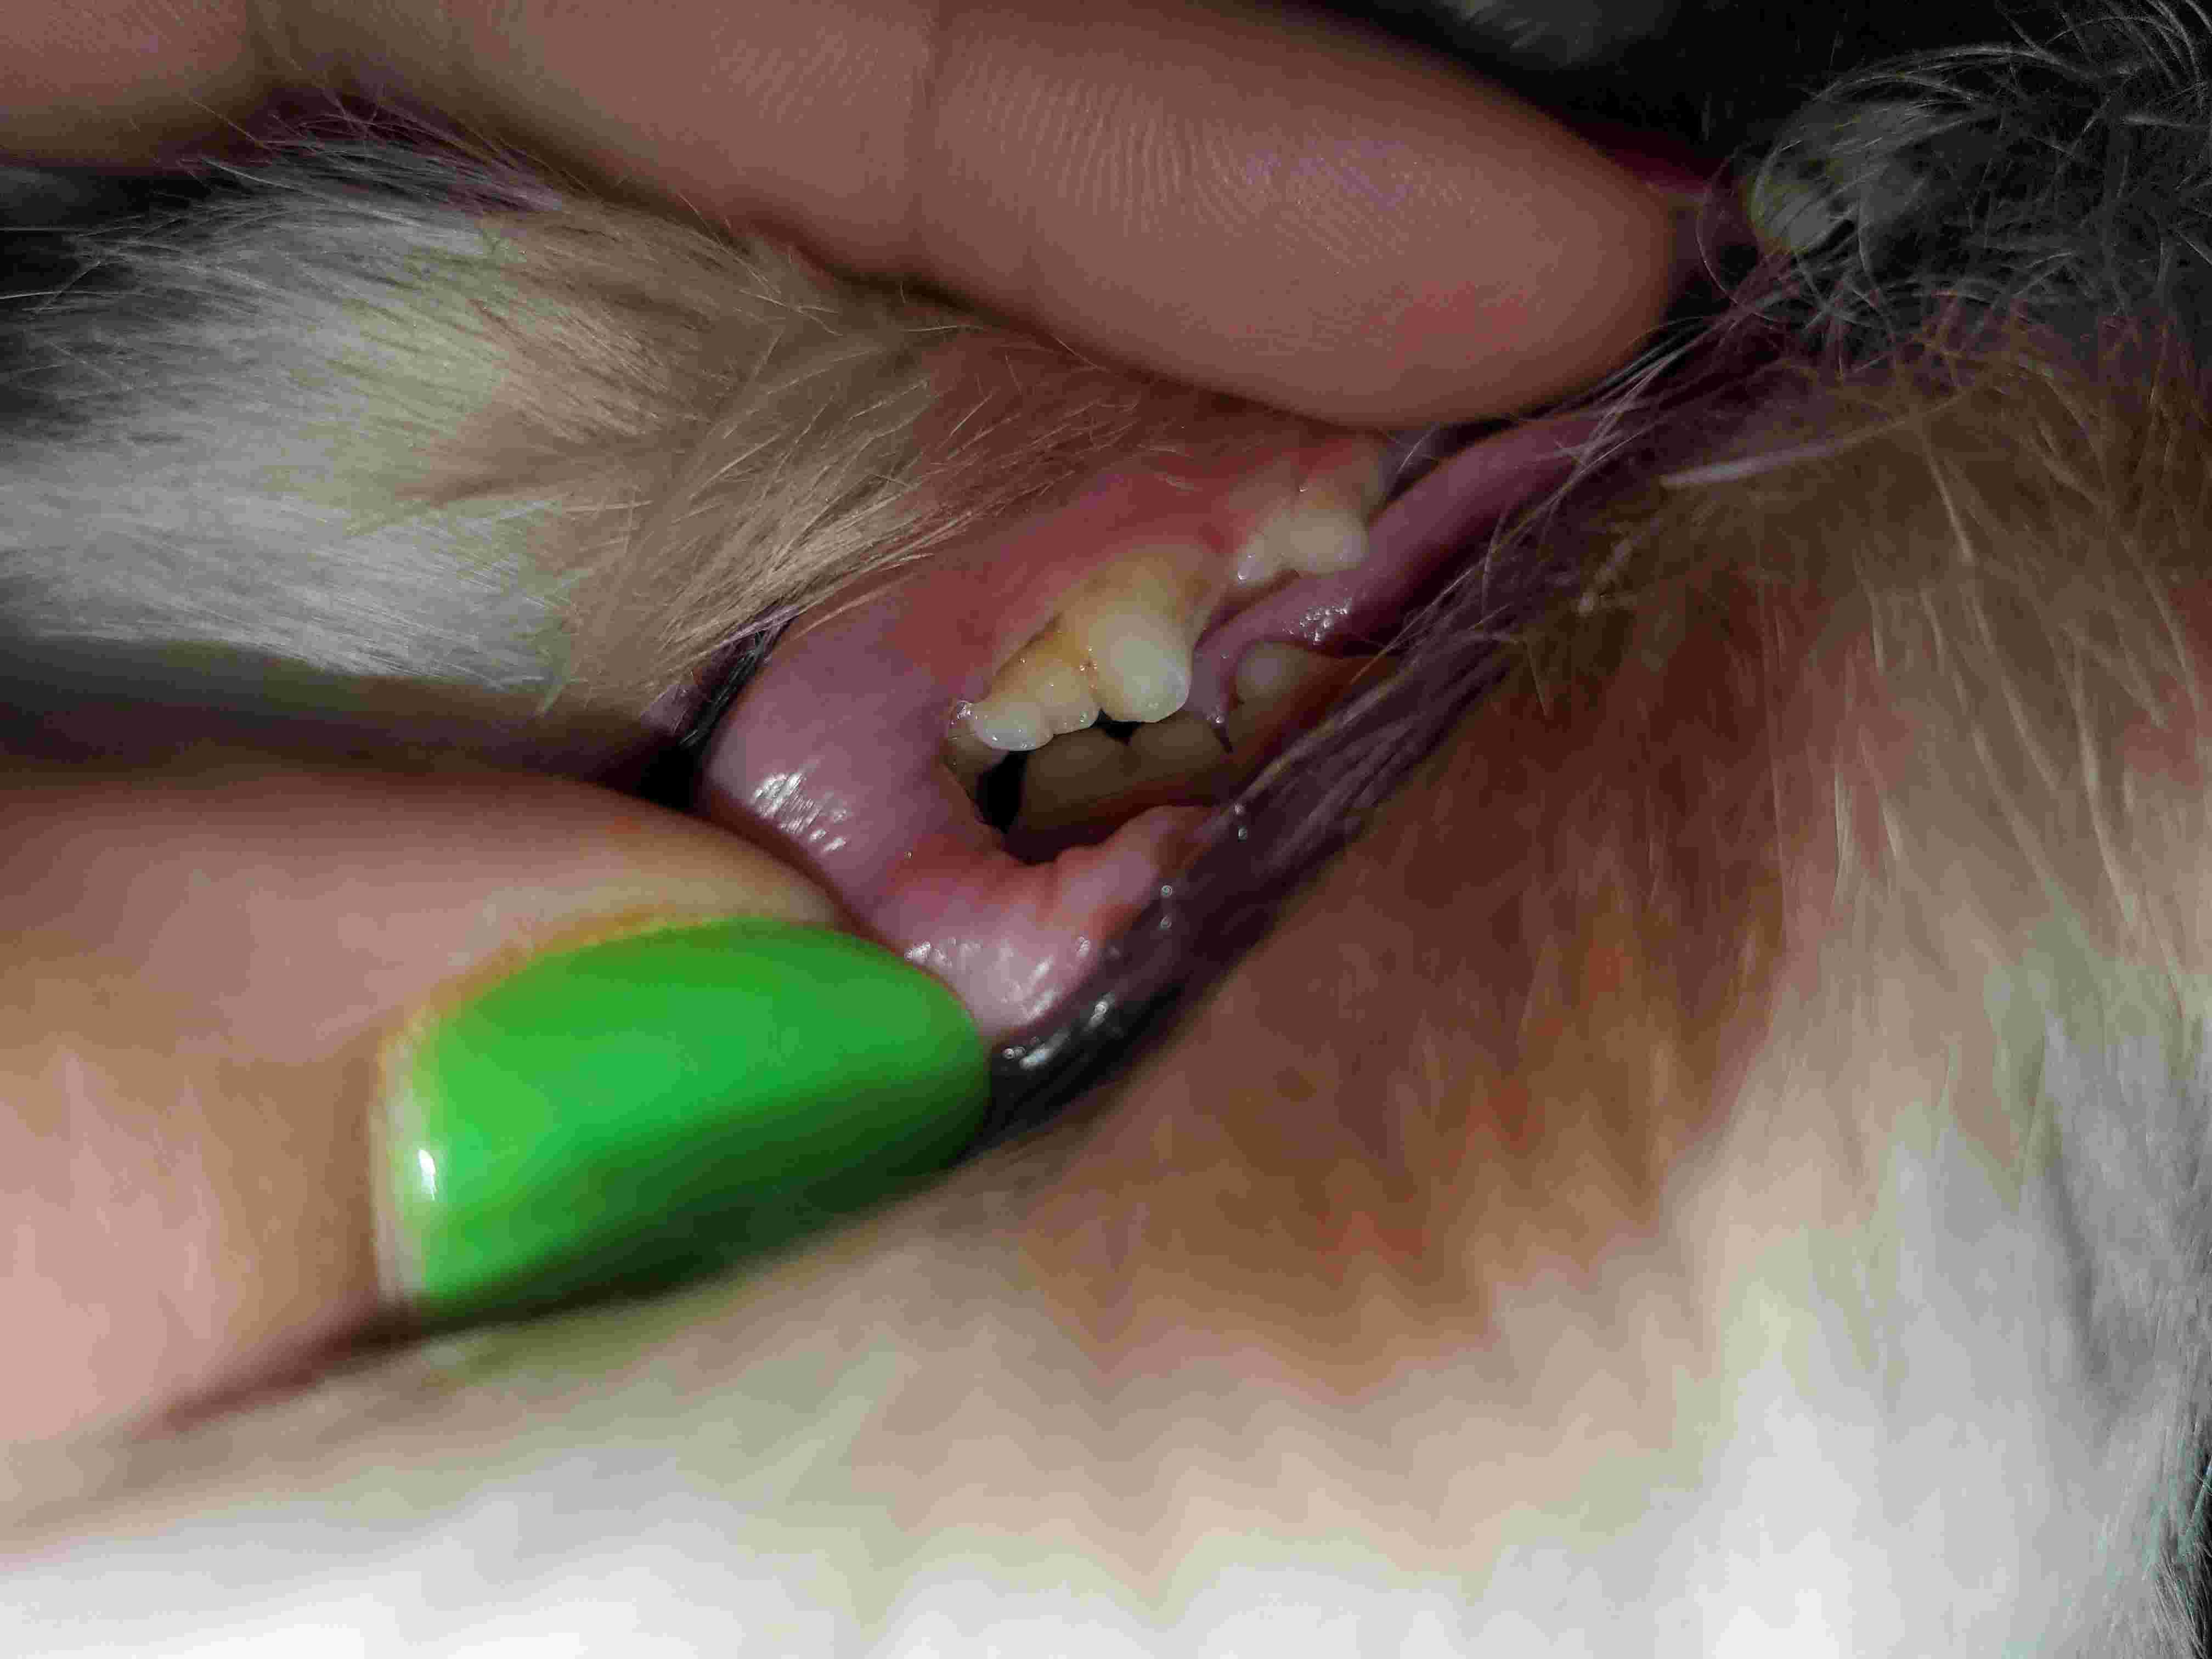

I was checking my dogs back teeth as I have been brushing them more frequently to help reduce tartar build up,because her previous owners must have never done so anyways today I thought I noticed a broken piece in her back tooth I'm not sure if it's just my over worrying but shes eating well,drink well and I touch it and she doesn't seem in any pain but again I'm no doctor. She is peeing and pooping fine too. I'm just curious as if I'm the only one seeing it

That may be a fracture tooth or an enamel defect. A close physical exam would likely be needed for confirmation of either. There doesn't appear to be any pulp exposure which is good. Monitor for decreased appetite, drooling or difficulty chewing on that side of the mouth. If you see any of these symptoms, have Harley examined by your veterinarian.